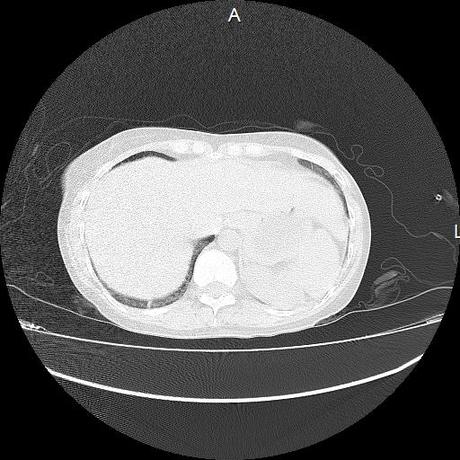

Se realiza volumen de tórax en fase simple, desde los opérculos torácicos hasta los hemidiafragmas, observándose:

El parénquima pulmonar con areas parcheadas difusas en vidrio despulido combinadas con otras areas hipodensas de baja atenuación debidas a atrapamiento aéreo y engrosamiento intersticial y zonas de fibrosis de predominio en lóbulos medios e inferiores de ambos pulmones.

Ambos hemidiafragmas sin evidencia de alteraciones.

- LOS HALLAZGOS PUEDEN ESTAR EN RELACIÓN A NEUMOPATIA INTERSTICIAL PROBABLE ETIOLOGIA HIPERSENSITIVA VS AUTOINMUNE/BACTERIANA/FUNGICA.